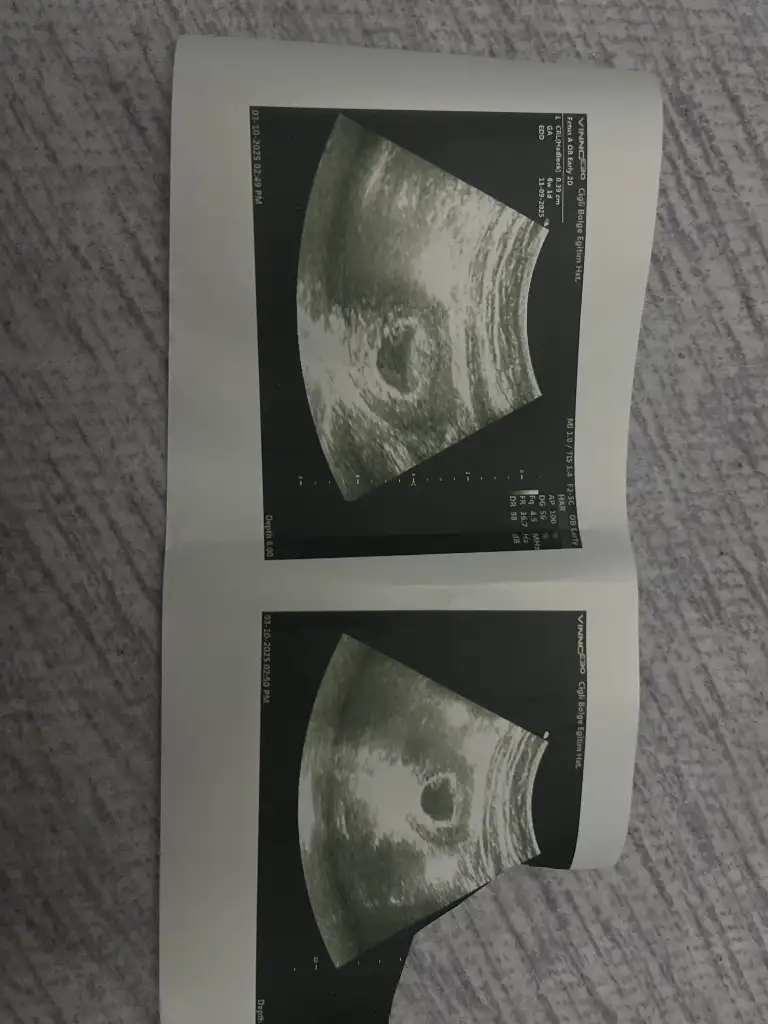

Merhaba 11. Hafta görüntüsü batından usg bakıldı yorumlar mısınızSelam Kızlarbir çok kişi gruplardan beni bilir. Yine yetiştim imdatlara

Merhaba. SAT’a göre 7+5. Abdominal ultrason.Selam Kızlarbir çok kişi gruplardan beni bilir. Yine yetiştim imdatlara